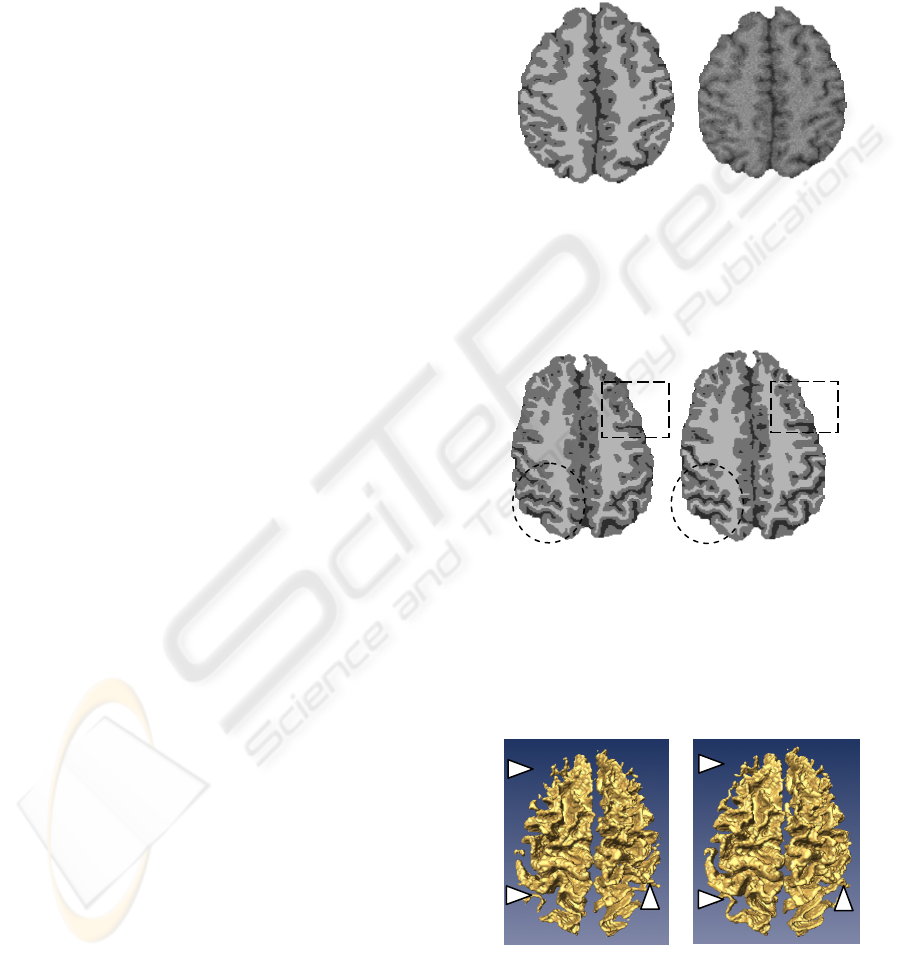

2.2 MRI Images

The local image information provided by α is very

helpful in the situation of low contrast, since it can

discriminate the three situations described above. As

known, the cortex of the brain has many

circumvolutions. Thus, it leads to intensity

variations in image, which can be easily described

by the multifractal analysis. In MRI images, the

sulcus can be considered as a valley in term of

intensity, and the CSF is generally at the bottom of

the valley. On the contrary, the gyrus can be

considered as a hill, and the white matter,

surrounded by the grey matter, is at the top of the

hill. The problems of the partial volume effects and

of the low contrast are essentially present in these

two types of regions. Most of the homogeneous

regions can be found within the white matter (in the